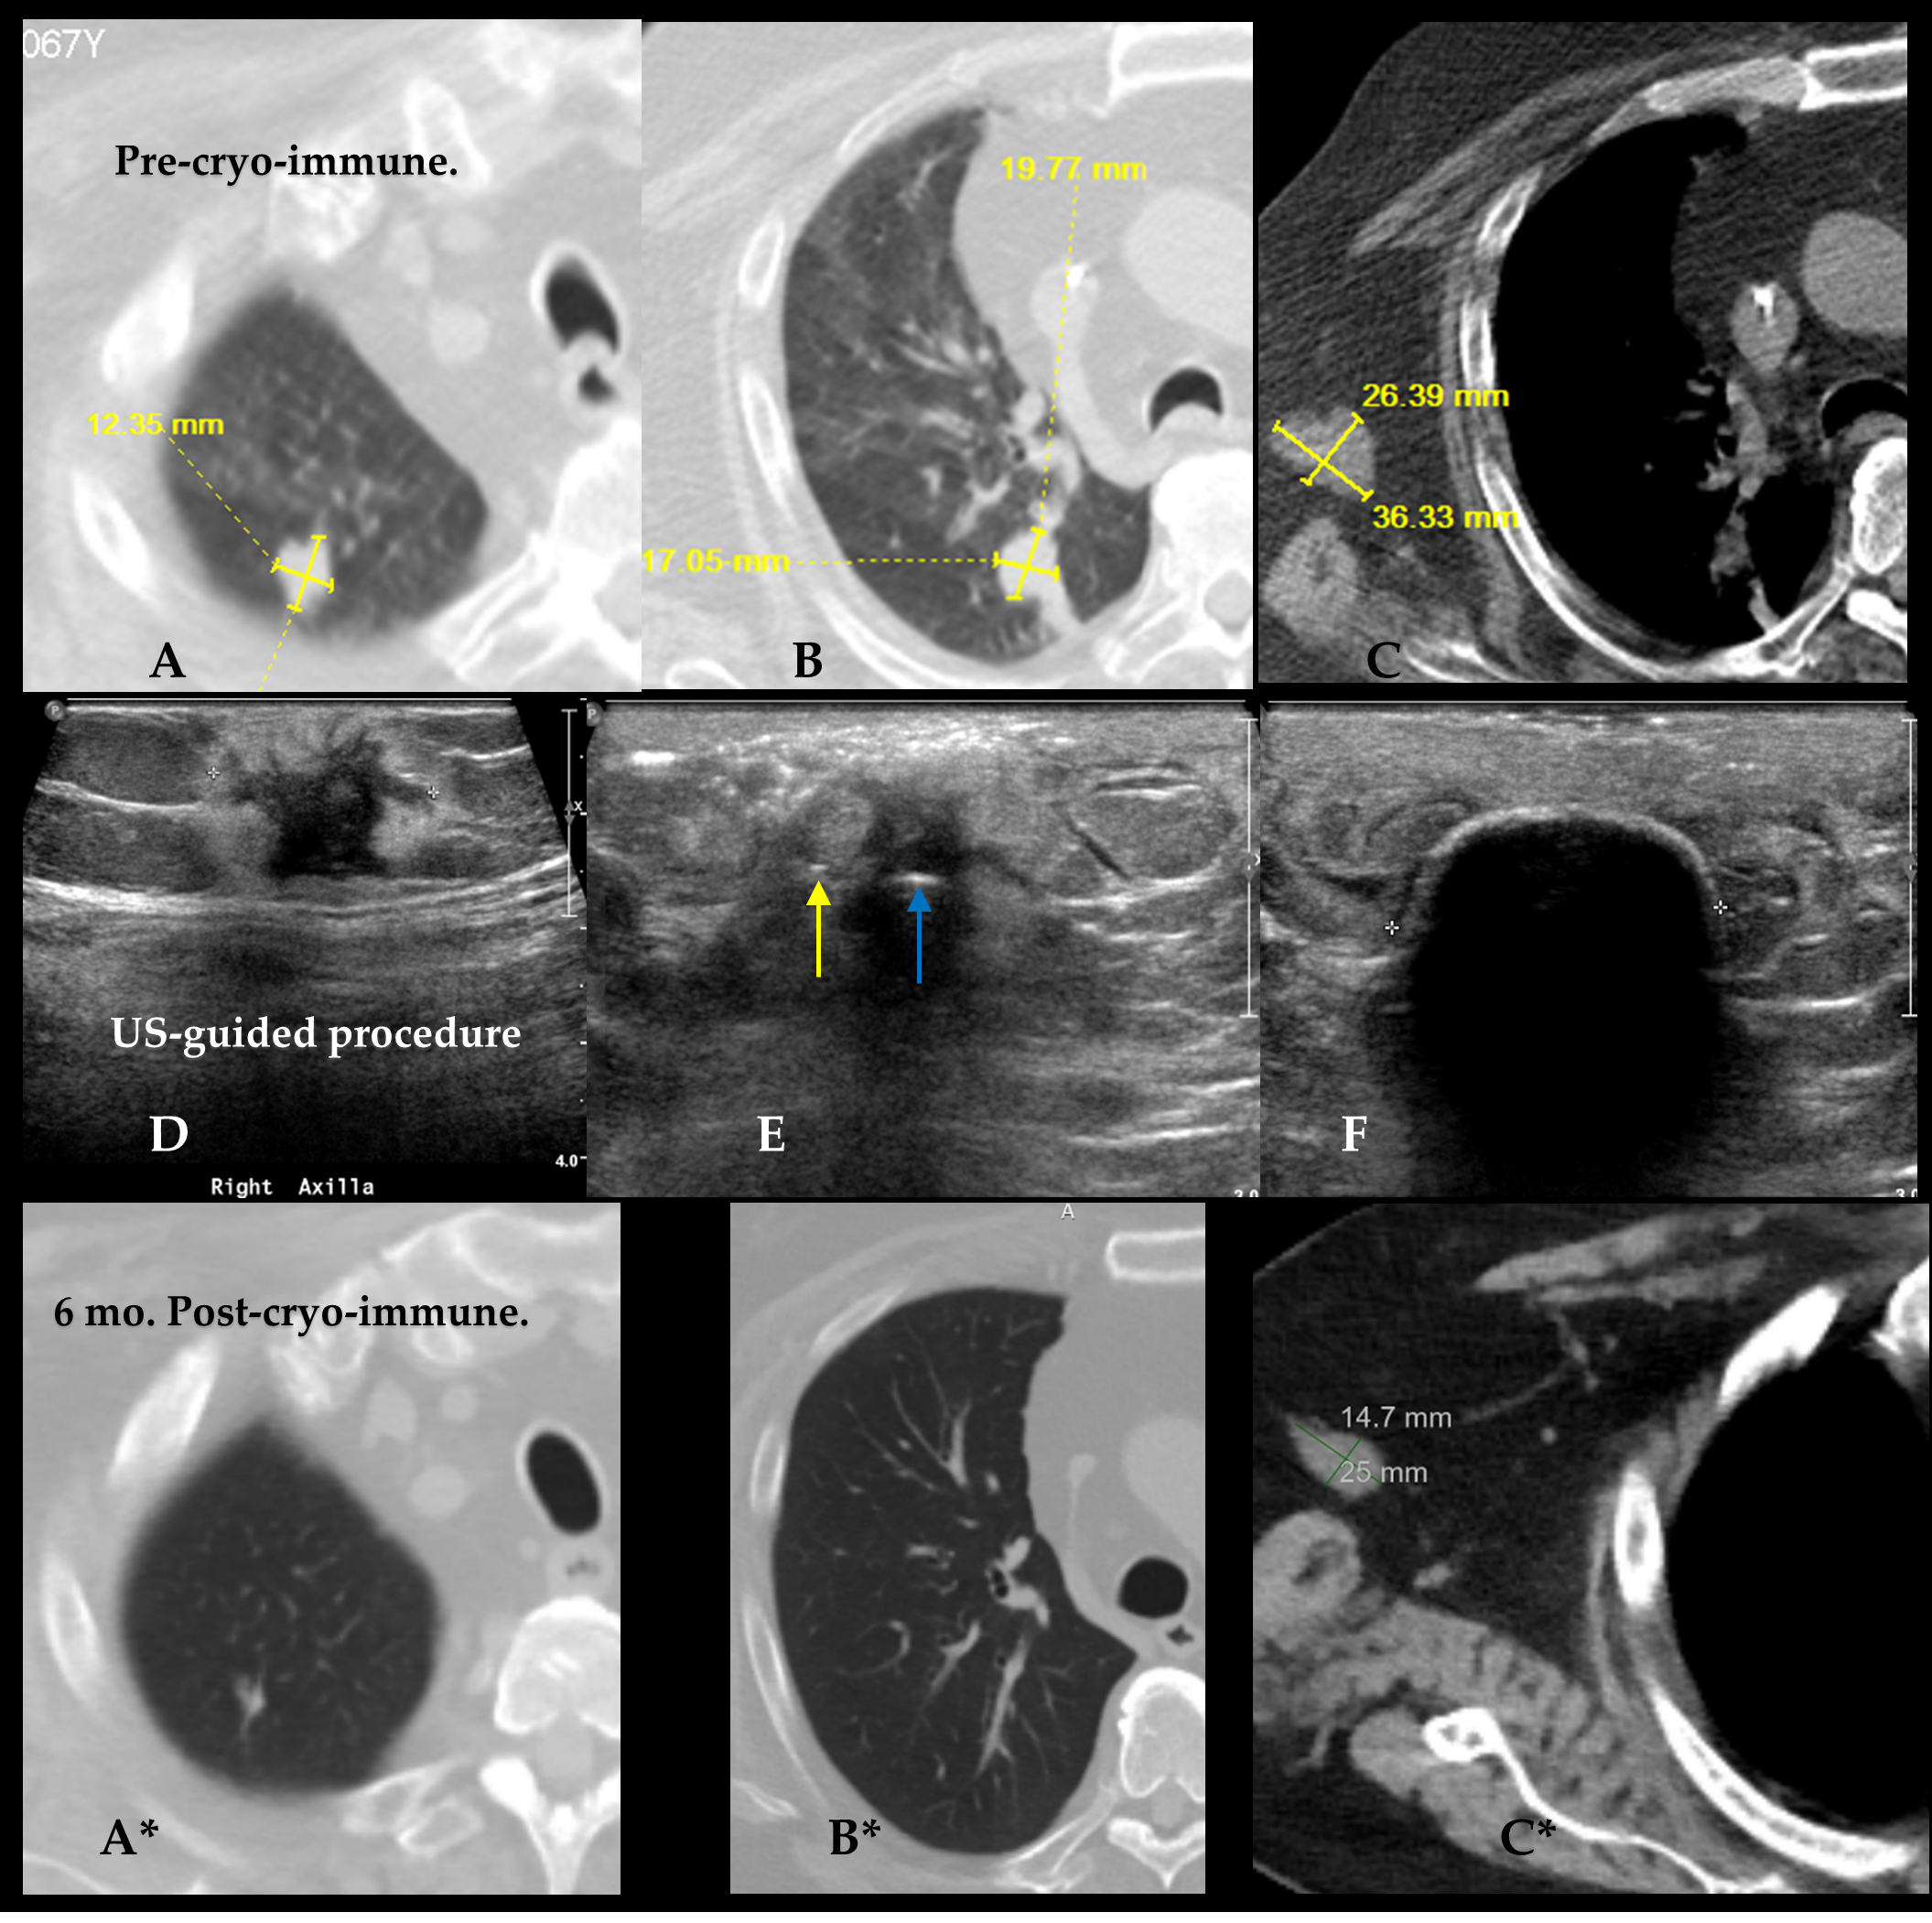

- Combined CT/US, image-guided cryoablation displays visible ice extending beyond tumor margins for improved local tumor control in patients with breast cancers > 1.5 cm.

- Appropriate cytotoxic isotherms need to volumetrically extend beyond all apparent tumor margins, which favors multi-probe cryoablation for tumors > 1.5 cm, whereas even larger single cryoprobes appear to be limited to breast cancers < 1.5 cm.